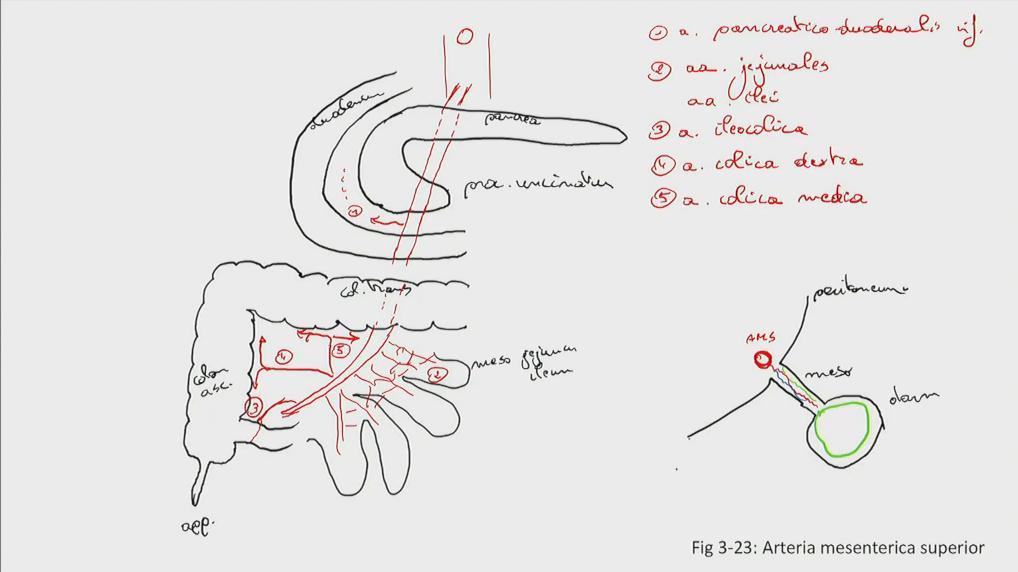

Fig 3.23: a. mesenterica superior (AMS)

|

|